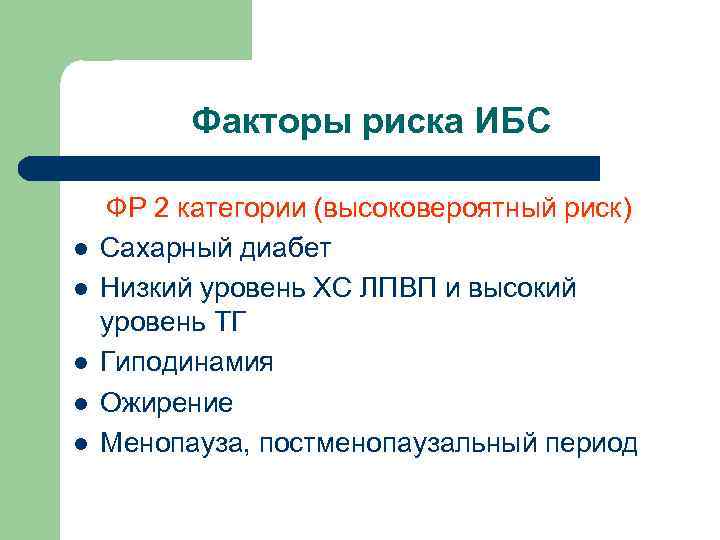

Факторы риска ИБС l l l ФР 2 категории (высоковероятный риск) Сахарный диабет Низкий уровень ХС ЛПВП и высокий уровень ТГ Гиподинамия Ожирение Менопауза, постменопаузальный период